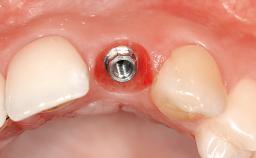

| Case Type | Single-Tooth Space |

| Jaw | Maxilla |

| Area | Posterior |